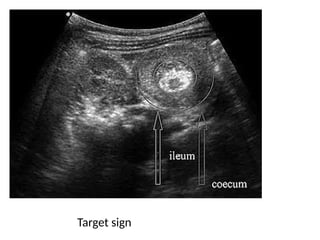

• Shows the classic “target sign” or “doughnut sign”

(layers of telescoped bowel).

• High sensitivity and specificity.

Target sign